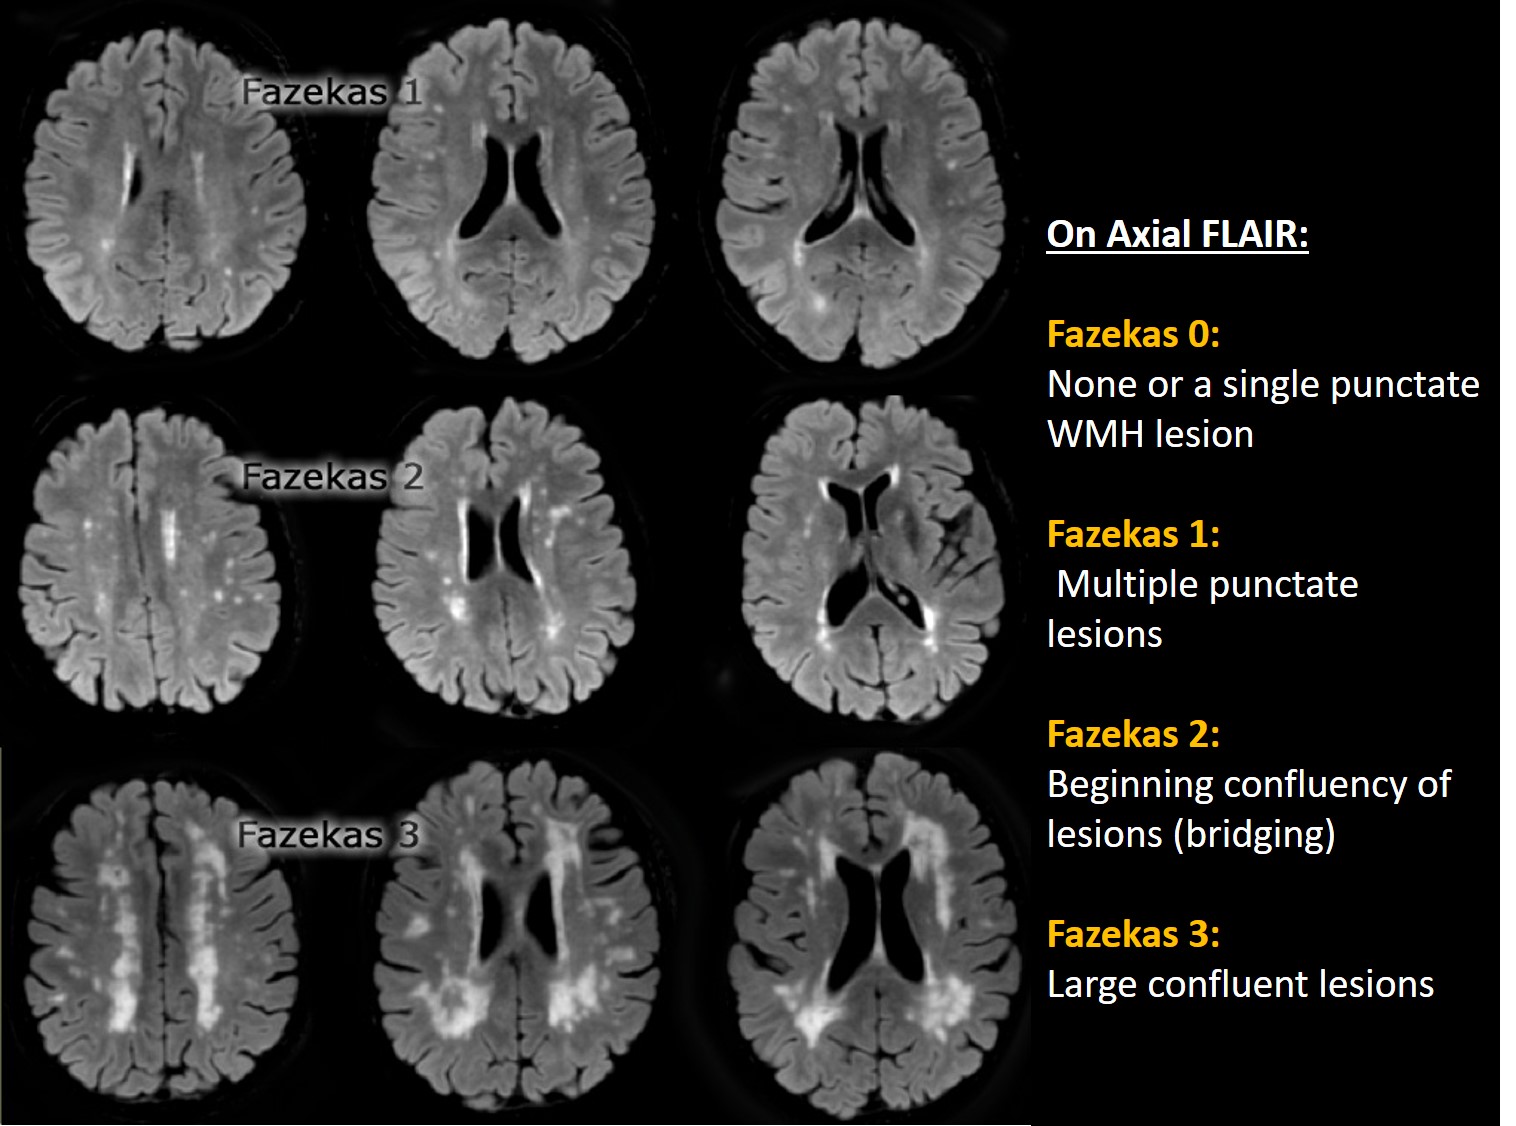

Fazekas grades. Лейкоареоз Фазекас. Fazekas 0. Фазекас 3. Фазекас классификация мрт.

Fazekas grades. Лейкоареоз Фазекас. Fazekas 0. Фазекас 3. Фазекас классификация мрт.

Fazekas grades. Fazekas степени мрт. Фазекас 2 мрт. Шкала Фазекас мрт. Лейкоареоз 3 степени по Fazekas.

Fazekas grades. Fazekas степени мрт. Фазекас 2 мрт. Шкала Фазекас мрт. Лейкоареоз 3 степени по Fazekas.

Fazekas grades. Классификация Фазекас. Fazekas мрт. Лейкоареоз степени по Fazekas. Фазекас классификация мрт.

Fazekas grades. Классификация Фазекас. Fazekas мрт. Лейкоареоз степени по Fazekas. Фазекас классификация мрт.

Fazekas grades. Фазекас классификация мрт. Лейкоареоз Fazekas 1 что это. Fazekas степени мрт. Лейкоареоз степени по Fazekas.

Fazekas grades. Фазекас классификация мрт. Лейкоареоз Fazekas 1 что это. Fazekas степени мрт. Лейкоареоз степени по Fazekas.

Fazekas grades. Фазекас 2. Fazekas 0. Фазекас 3.

Fazekas grades. Фазекас 2. Fazekas 0. Фазекас 3.